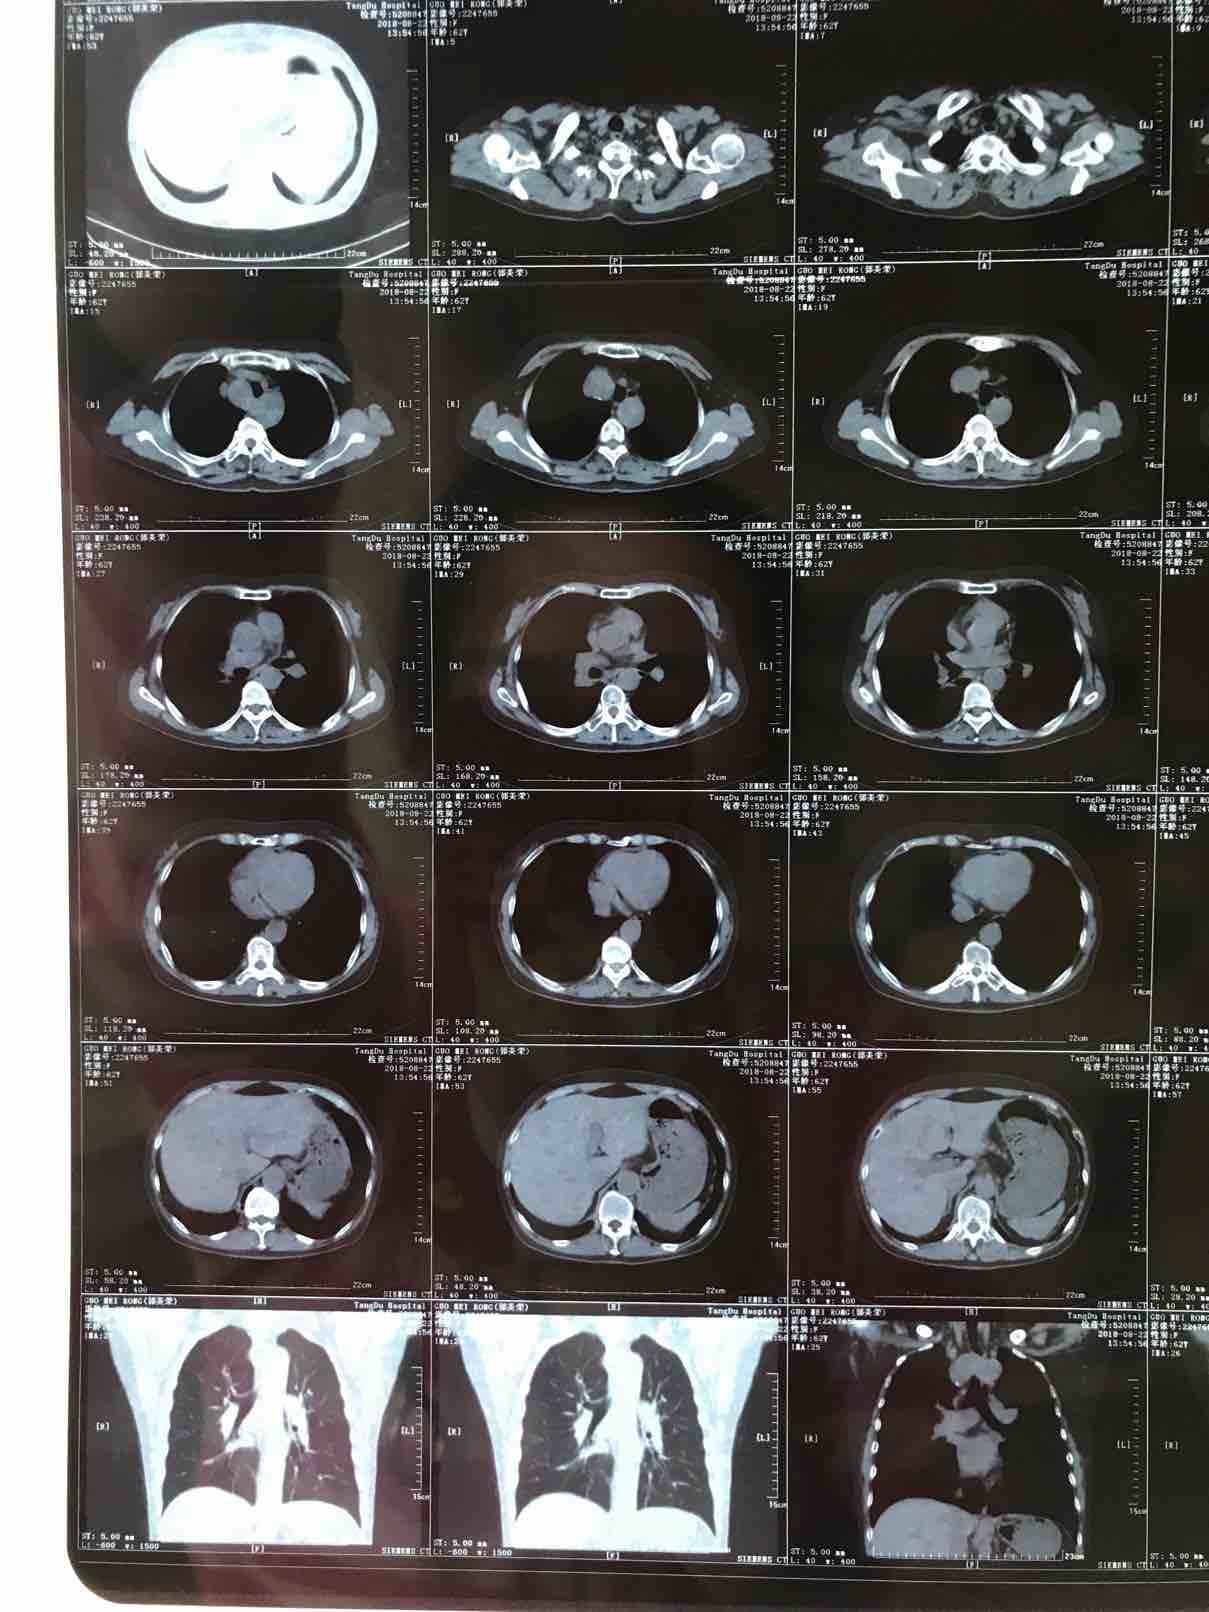

(2)

举报